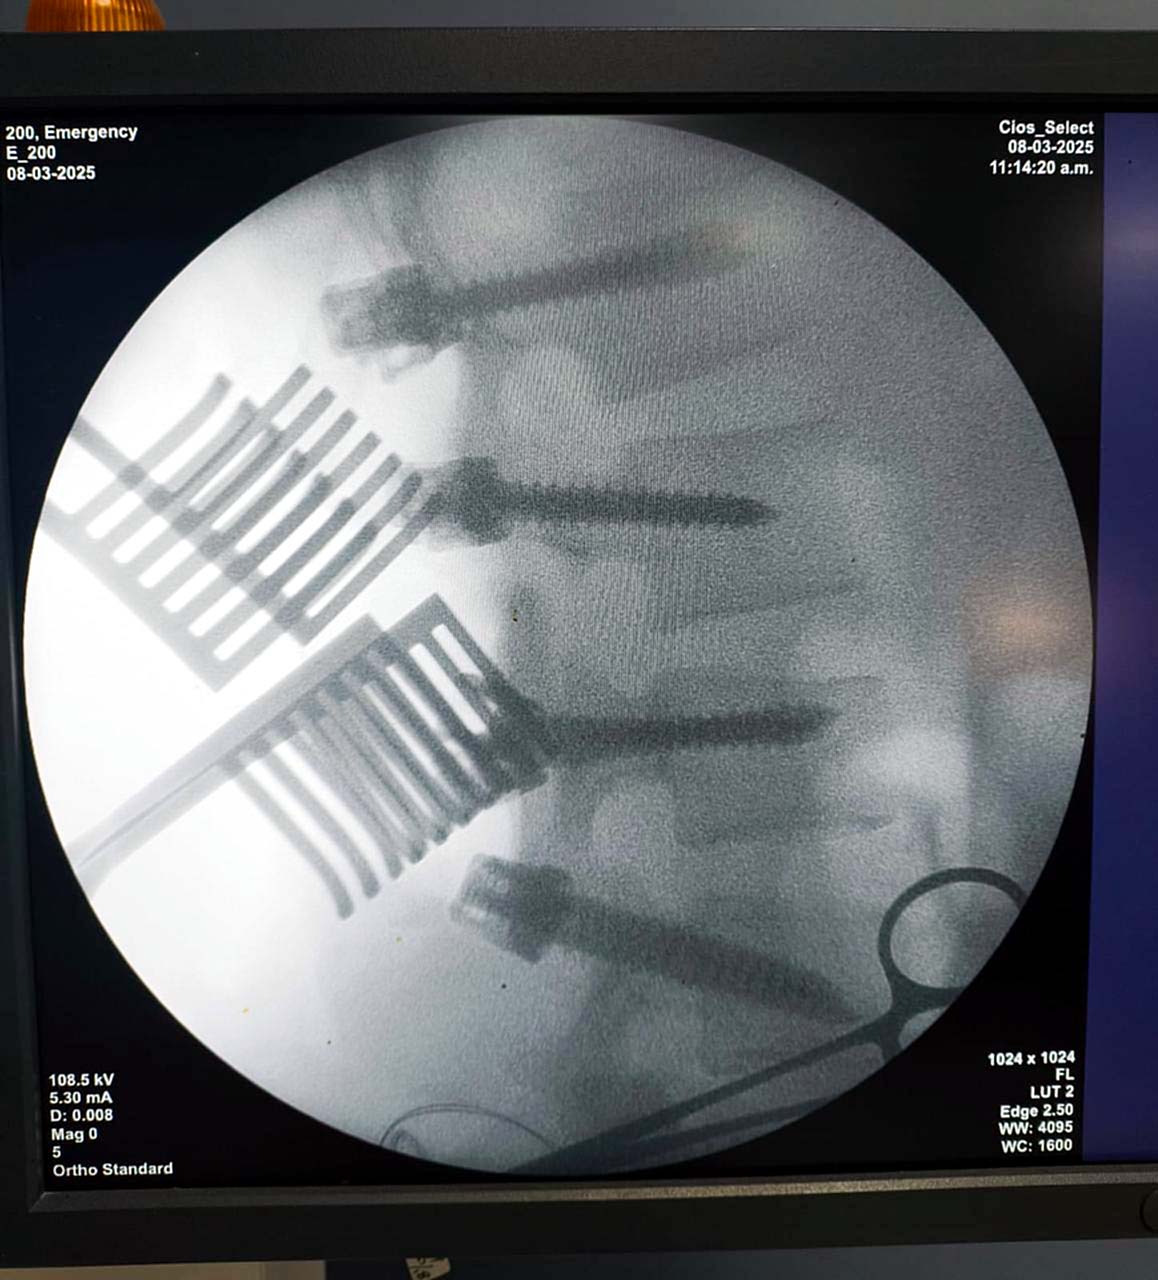

El equipo de Neurocirugía del IPS Ingavi realizó con éxito una intervención quirúrgica a un paciente de 18 años que sufrió un traumatismo de columna en un accidente de tránsito, resultando en una fractura lumbar. La cirugía, que duró 2 horas, consistió en una fijación con tornillos para estabilizar la lesión, y fue llevada a cabo con precisión por nuestros especialistas.

Afortunadamente, después de la cirugía, el paciente no tuvo problemas con el movimiento ni la sensación en las piernas, lo que refleja el éxito de la intervención. Ahora, se encuentra recuperándose y se moviliza sin dificultades, lo que significa que su recuperación va por muy buen camino.

Actualmente, el paciente se encuentra en sala estable y continúa bajo la supervisión y cuidados del equipo médico. Este tipo de intervenciones destaca la capacidad del equipo de Neurocirugía del IPS Ingavi para manejar casos complejos y ofrecer soluciones efectivas que garanticen la calidad de vida de los pacientes.